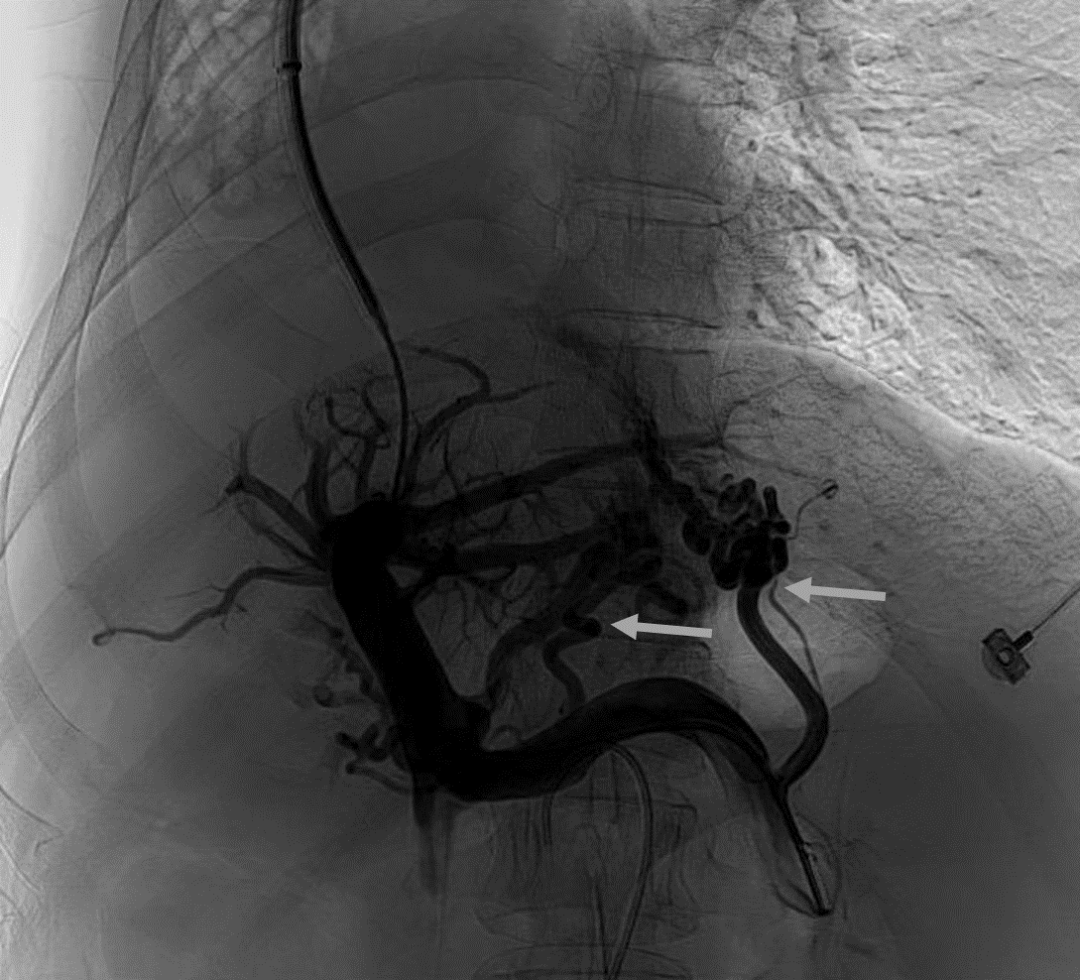

韓國宏教授介紹,TIPS手術是通過在肝靜脈與門靜脈之間的肝實質內建立分流通道,通過降低門靜脈壓力來預防和治療因門靜脈高壓引起的食管胃底曲張靜脈破裂出血或頑固性腹水。該手術不用開刀、創(chuàng)傷小、操作過程復雜、技術難度大、安全風險高,是目前外周血管介入中難度最大的手術之一。再加上人群中右位心發(fā)病率極低(約萬分之一),經(jīng)查閱文獻,在國內外尚未有類似病例報道,無經(jīng)驗參考。在右位心基礎上行TIPS術,無疑是難上加難。我們反復研究患者肝臟及心血管的特殊情況,詳細討論了手術方案,決定放棄常規(guī)的肝靜脈穿刺,另辟蹊徑,選擇高難度高風險的肝后段下腔靜脈穿刺門靜脈左支,憑借多年的經(jīng)驗和嫻熟的技術最終成功的在下腔靜脈與門靜脈之間放置了TIPS專用支架,術后門靜脈壓力梯度從術前的19mmHg降至3mmHg,曲張靜脈消失,解決了困擾曹女士多年上消化道出血的困擾?;颊咝g后第二天即可正常下床活動。